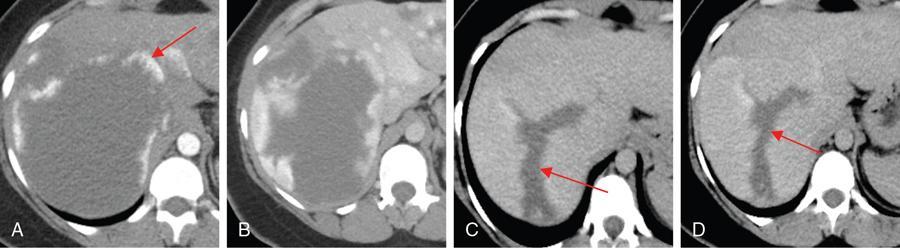

Ritu K. Kashikar, Shrinivas B. Desai, Pooja Punjani Vyas, Nilesh Doctor, Vivek Shetty Owing to advances in technology, focal liver lesions (FLLs) are increasingly encountered. Imaging particularly computed tomography (CT) and magnetic resonance imaging (MRI) play a vital role in diagnosis and characterization of FLL, thus avoiding unnecessary biopsies and interventions. Multiphase CT accurately diagnosis most liver lesions. Better soft tissue contrast and lack of ionizing radiation makes MRI a preferred modality in diagnosing FLLs. MRI with or without contrast for characterization of liver lesions regardless of preexisting liver disease has been assigned the highest rating as per American College of Radiology Appropriateness Criteria (Table 9.11.1). Solid lesions of epithelial origin Solid lesions of nonepithelial origin Pitfalls Cystic liver lesion Developmental cyst Infective cyst Miscellaneous Tmours of hepatocellular origin Tumours of nonepithelial origin Malignant cystic lesion Hepatic metastasis Ultrasound is often the initial modality for diagnosis and also the incidental detection of FLLs. Limitations to USG include the detection of small lesions less than 2 cm in size, particularly in patients who are cirrhotic or undergoing chemotherapy. Characterization of FLLs, involvement of crucial structures such as blood vessels, local staging and decisions such as operability are also not accurate with ultrasound alone and require confirmation with CT/MRI. The liver typically images in supine and left lateral positions. A curvilinear transducer with a frequency of 1.5 Hz is used. The subcostal diagonal, subcostal longitudinal or sagittal and transverse right intercostal lateral views are used. Right lobe of liver is imaged through an intercostal approach when the patient is taking deep inspiration. Subcostal view is used to image the three hepatic veins in one view. Transverse, longitudinal and oblique views of the liver are taken to image all the segments of liver. Colour and power Doppler have increased sensitivity for FLL detection, but sensitivity is still inferior to contrast-enhanced CT and MRI. The introduction of microbubble contrast agents (CAs) and the development of contrast-specific techniques have opened new perspectives in ultrasound of the liver. The technique is based on a new class of intravascular microbubble agents which contain perfluoro gases instead of air. This when combined with scanning modes sensitive to harmonic responses of microbubbles enable tissue signal suppression. The advent of the multislice technique and isotropic voxel have improved the spatial resolution of CT, allowing the recognition of small FLLs in difficult areas. Multislice CT has a sensitivity and specificity in the diagnosis of malignant FLLs of 63% and 64%, and 92 and 97%, respectively. Contrast media administration with dose based on the patient’s weight (approximately 600 mg iodine/kg of bodyweight), an iodine content of 350–400 mg/mL and a high injection rate of 4–5 mL/s are imperative to attain good contrast enhancement. Region of interest in the abdominal aorta and a threshold of 100 HU allows correct timing for threshold. A delay of approximately 18 s after the threshold provides the first arterial phase, allowing detection of hypervascular FLLs such as hepatocellular carcinoma (HCC). The late arterial phase is obtained approximately 10 s after the early arterial phase and shows progressive enhancement of hypervascular lesions, improving detection rate, while the optimal hepatic enhancement in the portal phase is reached approximately 50–60 s after the threshold. Portal venous thrombi are also best detected in this phase. The venous phase aids in the detection of washout, hepatic venous thrombosis. Delayed phase is often required in lesions such as cholangiocarcinoma and haemangioma, which show progressive enhancement (Table 9.11.2, Fig. 9.11.1). Delayed phase images are required for tumours such as cholangiocarcinoma and large haemangiomas, which reveal delayed enhancement. As mentioned previously, MRI is the modality of choice in diagnosis of FLLs. Most FLLs appear hyperintense on T2W1 images with varying intensity depending upon the water content and flow dynamics. FLLs are typically hypointense on T1W1 images with the exception of fat containing, haemorrhagic lesions and those containing chelates of metals like regenerating/dysplastic nodules. In- and opposed-phase images help in detection of intralesional fat. Diffusion-weighted images are beneficial particularly in noncirrhotic population and best suited in detection of metastasis. Postcontrast images obtained with extracellular agents are parallel to those obtained with CT (Fig. 9.11.2). The pre- and postcontrast MRI protocol is mentioned in Table 9.11.3. T2-weighted single-shot fast spin-echo (SE) T1-weighted in- and opposed-phase GRE Dynamic 3D T1-weighted FS spoiled GRE (in hepatic arterial, portal venous and equilibrium phases) There are two main categories of CAs used in liver imaging – the extracellular and the hepatocyte-specific (Fig. 9.11.3). Extracellular agents are more widely used and provide information similar to contrast-enhanced CT study. The advantage of the other category of CAs, that is, hepatocyte-specific agents, is the ability to provide this extracellular information with added benefit of delayed phase information. Tumours of hepatocellular origin with functioning hepatocytes take up and biliary excretion with take up and retain these agents appearing isointense to background liver. Lesions without functioning hepatocytes fail to retain contrast and hence appear hypointense to background liver on delayed phase. This allows better detection and characterization of focal liver lesion particularly those lesser than 2 cm (Table 9.11.4). Haemangioma is the most common benign hepatic tumour. The incidence in general population varies from 1% to 20%. Females have a higher preponderance with variable female to male ratios of 2:1 to 5:1. Imaging in particular MRI has high reliability in diagnosing classic haemangioma. The sensitivity and specificity of MRI is greater than 90% in diagnosis. The aetiology of haemangioma is unknown. Since haemangiomas are known to run in families, a genetic origin has been implicated, while other mesenchymal tumours are thought to be congenital. Most patients are asymptomatic and often the lesion is discovered as an incidental finding. Pain in the right upper abdomen is the most common complaint; others include loss of appetite, nausea, vomiting and abdominal discomfort. Symptoms are usually seen in large haemangiomas or those with complications. Liver function tests and tumour markers like AFP and CA19.9 are within normal limits. Blood-filled cavities of varying sizes lined by flat endothelial cells and supported by fibrous connective tissue are seen on histology. Three histological subtypes have been described: the capillary haemangioma, the cavernous haemangioma and the sclerosing haemangioma. The imaging features of a haemangioma depend on its size; typical haemangiomas are mostly less than 3 cm in diameter. Haemangiomas are hyperechogenic, homogeneous lesion presenting a posterior acoustic enhancement (Fig. 9.11.3). The hyperechogenicity of haemangiomas is related to the interfaces between vascular spaces, fibrous stroma and the slow blood flow. Typically, haemangiomas have slow flow and hence do not show vascularity on colour or power Doppler. The sensitivity and specificity of ultrasound in differentiating haemangioma from other malignant lesions are high, with values of approximately 94.1% and 80%, respectively, for lesions less than 3 cm in diameter. Unlike HCC, no flow is seen on colour Doppler. A peripheral echogenic rim around hypoechoic lesions can suggest haemangioma. On the contrary, perilesional hypoechoic rim called the target sign is seen in lesions such as metastasis (Table 9.11.5). Adenomas can be distinguished on the basis of the absence of posterior acoustic enhancement and characteristic pattern of peripheral vascularity seen in adenoma. Another differential diagnosis to be considered is focal nodular hyperplasia (FNH), which has the characteristic ‘spoke-wheel sign’. Contrast-enhanced ultrasound (CEUS) improves specificity for the diagnosis of haemangioma. The vascularity pattern with contrast-enhanced USG is similar to that seen with CT. The typical hemangioma (HH) shows peripheral nodular enhancement in the arterial phase with complete (but sometimes incomplete) centripetal filling in the portal venous and late phases. This particular pattern of enhancement helps in differentiating haemangiomas from other lesions like adenomas, FNH, HCC or metastasis. This characteristic enhancement pattern has a sensitivity of 98% for histologically proven HH. One should be aware that an HH can rarely have a centrifugal enhancement. Computed tomographic (CT) findings consist of a hypoattenuating lesion on nonenhanced images. Haemangiomas show peripheral discontinuous nodular enhancement on arterial phase of dynamic contrast-enhanced CT. The density of the nodules is equivalent to that of the aorta. Centripetal filling with is seen on venous phase, which progresses to uniform enhancement. The enhancement persists on delayed phase (Fig. 9.11.4). Washout of contrast on delayed phase is not seen in haemangioma and if seen, alternate diagnosis must be considered. This classical pattern of enhancement cannot be highlighted in very small lesions of less than 5 mm, which can be difficult to characterize. In patients with severe fatty infiltration of the liver, HH can appear hyperdense relative to the adjacent liver parenchyma on nonenhanced scan. Haemangiomas are hyperintense on T2-weighted images, which is identical to that of cerebrospinal fluid. T2 hyperintense signal is classically described as ‘light bulb bright’. Malignant lesions of the liver do not appear as bright on T2W1 images. They appear hypointense to adjacent liver on T1-weighted images. Long relaxation T2W1 images further improve accuracy in diagnosis of haemangiomas and help in differentiation from metastasis. Haemangiomas, unlike other liver lesions retain hyperintense signal on long relaxation T2W1 images. A threshold of 112 ms has 92% accuracy, 96% sensitivity and 87% specificity for differentiating haemangiomas from metastasis. On gadolinium administration, the enhancement pattern is similar to that seen with iodinated contrast on CT. Classic enhancement pattern in combination with characteristic T2 appearance are diagnostic for haemangioma (Fig. 9.11.5). Certain pitfalls exist in diagnosing haemangiomas using gadoxetate disodium. Due to the lack of hepatocytes, haemangiomas appear hypointense to the background liver on delayed hepatocyte phase and mimicking malignant process (Table 9.11.6). Lesions shown peripheral nodular arterial enhancement (Table 9.11.7): On fluorodeoxyglucose-positron emission tomography (FDG-PET)/CT, most hepatic haemangiomas appear low-attenuation lesions with FDG avidity equal to background liver parenchyma and are easily determined to be benign. However, a small percentage of haemangiomas may be FDG-avid. If an FDG-avid hepatic lesion demonstrates the characteristic enhancement pattern, this is consistent with an FDG-avid haemangioma. Technetium-99m pertechnetate-labelled red blood cell scintigraphy has high specificity in the diagnosis of haemangiomas. In this technique, there is decreased activity in haemangiomas on early images and increased activity on delayed blood pool images. Therefore, radionuclide scintigraphy has a sensitivity of 78% and an accuracy of 80% and may be a valuable tool when the diagnosis cannot be achieved with other imaging modalities. Large haemangiomas are often heterogeneous with internal clefts and septae. They are termed as giant haemangiomas when they exceed 4 cm in diameter. Discrepancies are there in definition with some authors defining giant haemangiomas as lesions greater than 6 cm or 12 cm in diameter. These may cause symptoms of abdominal pain and distension. These haemangiomas demonstrate changes such as haemorrhage, thrombosis, extensive hyalinization, liquefaction and fibrosis. The central cleft-like area may be due to cystic degeneration or liquefaction. On USG, they reveal heterogeneous echotexture. They are hypoattenuating and heterogeneous on nonenhanced CT with central areas of low attenuation. After intravenous administration of contrast material, the typical early, peripheral and globular enhancement is observed. These may show irregular or ‘flame-shaped’ discontinuous peripheral enhancement as opposed to typical nodular enhancement pattern seen in smaller haemangiomas. Although centripetal pattern of enhancement is seen during the venous and delayed phases, the filling-in incomplete. Central scars are defined in this subset of haemangiomas (Fig. 9.11.6). At MRI, T2-weighted images show a markedly hyperintense cleft-like area and some hypointense internal septa within a hyperintense mass. On delayed phase, incomplete filling and central scar are seen similar to CT (Fig. 9.11.7). Complications include intratumoural haemorrhage, inflammatory changes or consumptive coagulopathy (Kasabach–Merritt syndrome). These may warrant management such as arterial embolization or resection. This pattern is seen 16% of all haemangiomas, and is seen more often in small haemangiomas (42% of haemangiomas) <1 cm in diameter. CT and MRI show immediate homogeneous enhancement at arterial phase CT or contrast-enhanced MRI. The size of the blood spaces is the reason for difference in enhancement pattern. Smaller the lesion, smaller the size of blood spaces and faster the rate of spread of contrast material. These lesions usually show perilesional halo of hyperenhancement on the late arterial phase, which is believed to be due to arteriovenous shunting. Rapid arterial enhancement makes these haemangiomas difficult to distinguish from hypervascular metastasis (Table 9.11.8). However, washout of contrast is seen from haemangiomas on delayed phase (Fig. 9.11.8). Hepatic haemangiomas rarely demonstrate calcifications, while haemangiomas in other locations frequently demonstrate phleboliths. Calcified haemangiomas are mostly found incidentally. Calcifications may occur in the marginal or central portion of the lesion and consists of multiple spotty calcifications, which correspond to phleboliths. However, large, organized calcifications are also possible. Some calcified haemangiomas may demonstrate poor enhancement. Hyalinized hepatic haemangiomas are rare. It has been suggested that hyalinization represents an end stage of haemangioma evolution. These haemangiomas are usually asymptomatic. The radiological features of a haemangioma are completely altered ones hyalinization occurs; hence biopsy is often mandatory for diagnosis. Hyalinized haemangiomas show only slight high signal intensity on T2W1 images. There is lack of early enhancement on dynamic contrast-enhanced images (Fig. 9.11.9). Fluid–fluid levels within haemangiomas are very rare. Fluid–fluid levels are seen both with CT and MRI with inferior layer representing the red blood cells and superior layer unclotted serous blood. Dependent hyperdensity/T1 hyperintensities can be seen corresponding with dependent haemorrhage. Pedunculated haemangiomas are very rare. They can be asymptomatic or complicated by subacute torsion and infarction. Typical enhancement pattern and signal on T1 and T2W1 images are clues to the diagnosis. Capsular retraction is usually associated with malignant tumours such as cholangiocarcinoma, epithelioid haemangioendothelioma or metastases. Rarely, it has been seen in haemangiomas. A possible mechanism could be fibrous degeneration. Multiple haemangiomas are seen in 10% of cases and usually show classical imaging features. Fatty infiltration of liver may alter the imaging appearances of lesions. Haemangiomas appear slightly hyperechoic, isoechoic or hypoechoic relative to the fatty liver. At nonenhanced CT, the lesion may be hyperattenuating relative to the liver. Contrast-enhanced CT shows peripheral enhancement and delayed filling, an appearance similar to that of a haemangioma in a normal liver. Haemangiomas are less common in setting of cirrhosis and may be difficult to diagnose due to sclerosis. Complications are seen in 4.5%–19.7% and often seen in large lesions such as inflammation, coagulation within can lead to systemic disorders, haemorrhage would lead to haemoperitoneum, volvulus and adjacent organ compression. Irrespective of the size, treatment is indicated only for haemangiomas with significant symptoms, those developing complications, or when there is an inability to exclude malignancy. Attempt should be made to exclude other causes of the patient’s symptoms. The term focal nodular hyperplasia (FNH) was introduced in 1958 by Edmondson. In 1995, the International Working Party classified FNH with other regenerative lesions, and not a neoplastic lesion. It is defined as a nodule consisting of normal appearing hepatocytes occurring in a histologically normal liver. It is the second most common tumour of the liver after haemangioma with a reported prevalence of 0.9%. The lesion is more commonly seen in females with female to male ratio of 8:1. Multiplicity is seen in 20% of patients. The combination of multiple FNH lesions and haemangiomas is considered to be multiple FNH syndrome. Vascular malformation and vascular injury have been suggested as the underlying mechanism. An association with steroids has been denied more recently. FNH has been classified as classic and nonclassic varieties. These have been discussed in Table 9.11.9. Classic FNH is characterized by abnormal nodular architecture, malformed vessels and cholangiolar proliferation. Nonclassic FNH lesions lack one of the following classic features – nodular abnormal architecture or malformed vessels – but always show bile ductular proliferation. Classic FNH on gross appearance shows lobulated contours with multiple nodules surrounded by fibrous septae originating from a central scar, which contains a vascular malformation. On histopathology, nodular hyperplastic parenchyma is seen in classic FNH. Circular or short fibrous septae surround these nodules completely or incompletely. Thickening of the hepatic plates is seen. Fibrous connective tissue, cholangiolar proliferation with surrounding inflammatory infiltrates and malformed arteries, capillaries, vascular channels of undetermined type and veins are seen in the central scar. The arterial blood in FNH shows centrifugal distribution from anomalous central arteries. Fatty infiltration is seen in approximately 50% of lesions, while signs of hepatic steatosis are seen in approximately 20% of cases with classic FNH. Variable amounts of Kupffer cells are seen in both classic and nonclassic variants. Nonclassic FNH is heterogeneous and on gross appearance resembles adenomas in most cases, with vaguely lobulated contours and lack of a macroscopic central scar. The histology varies with subtypes. Subtypes of nonclassic FNH include telangiectatic type, mixed hyperplastic and adenomatous forms and FNH with cytologic atypia. The histological features of these are described in Table 9.11.10. At US, typical FNH is often not well visualized. The lesions may be slightly hypoechoic, isoechoic or slightly hyperechoic. The compressed liver tissue form a hypoechoic halo around the lesion, which appears more prominent in patients with fatty infiltration. A prominent central scar may improve the conspicuity of the lesions. Use of colour and power Doppler US shows vascularity in suspected FNH. On contrast-enhanced USG, FNH is hyperenhancing in the arterial and portal venous phases in more than 90% of cases. The arterial enhancement patterns include central (60%–70% of cases) or eccentric (<20% of cases) with centrifugal filling, but sometimes are homogeneous. Multiphase CT is an excellent modality for detection and characterization of FNH. These lesions classically show a lobulated contour. At unenhanced CT, the lesions are either hypoattenuating or isoattenuating to the surrounding liver. In the arterial phase, the lesions show homogeneous intense enhancement except the central scar and fibrous septa. In the portal and later phases, the lesions become more isoattenuating with the surrounding liver. The central scar reveals enhancement on delayed phase (Fig. 9.11.10). This feature helps distinguish from other lesions with central scar-like fibrolamellar carcinoma. A vascular malformation can be seen in the central scar in some cases (Fig. 9.11.11). There may be enlarged hepatic veins in the vicinity of the mass. FNH do not have portal venous drainage. The drainage is essentially into hepatic venules, hence the enlarged adjacent veins. The central scar is often not identified in small FNH lesions. In a study, 80% of FNH lesions less than 3 cm lacked visible central scar. The sensitivity and specificity of MRI in diagnosis of FNH are 70% and 98%, respectively. The central scar is more often detected with MRI than with CT (78% and 60%, respectively). FNH is typically iso- or hypointense on T1-weighted images (94%–100%) and is slightly hyperintense or isointense on T2-weighted images (94%–100%). The lesions may not be very conspicuous on T2W1 images. The central scar is hyperintense on T2-weighted images in 84% of cases. FNH shows intense homogeneous enhancement in the arterial phase. The enhancement pattern in arterial phase may be nodular, resembling a popcorn, the result of intralesional fibrous septae. Mosaic pattern of heterogeneous enhancement seen in malignant lesions is not seen in FNH. Central vascular malformation may be seen in early phases. These lesions classically fade to isointensity on delayed phase with the exception of the central scar (Fig. 9.11.12). FNH may show a pseudocapsule, which results from compression of the surrounding liver parenchyma by the FNH, perilesional vessels and inflammatory reaction. The pseudocapsule may show enhancement on delayed contrast-enhanced images. A central scar is present at imaging in most patients with FNH. The central scar is hyperintense on T2W1 and hypointense on T1W1 images. The presence of inflammation and vessels within the scar are responsible for the hyperintense signal (Fig. 9.11.13). The scar does not enhance on early phases of contrast study and shows enhancement on delayed phases of dynamic study. The scar is absent in 30% of cases. The hepatocyte-specific CA gadoxetate disodium can be useful in distinguishing FNH from other lesions like adenomas. Densely packed functioning hepatocytes and abnormal blind-ending bile ductules in FNH result in contrast retention and delayed biliary excretion. FNH often shows enhancement on delayed images using gadoxetate disodium, and along with radiating fibrous septae, it may result in a characteristic spoke-wheel appearance. On the contrary, hepatocellular adenomas (HCAs) are usually hypointense to liver on hepatocyte phase images because they lack bile ductules. Superparamagnetic iron oxide (SPIO) is a negative reticuloendothelial-specific CA taken up primarily by the hepatosplenic Kupffer cells. This agent shortens T2 relaxation time predominantly, leading to a significant decrease of SI of normal hepatic. FNH contains Kupffer cells and hence shows significant signal drop after administering SPIO. This CA is, however, not commonly used particularly with advent and increased usage of hepatocyte-specific agents (Table 9.11.11). These lesions have high signal intensity on T2-weighted images, a central scar with low signal intensity on T2-weighted images, a prominent pseudocapsule and incomplete intense enhancement of the lesion. Extreme heterogeneity can be seen in these lesions leading to difficulty in distinguishing from malignant lesions such as HCC and cholangiocarcinoma. Biopsy and histopathology diagnosis are often needed in this subset. Telangiectatic FNH may show areas of haemorrhage. A French study has reported an association of 23% between FNH and haemangiomas. The incidence of coexistence of FNH and adenoma is lower (3.6%). There have also been reports of rare associations of FNH with other types of vascular anomalies like congenital absence of the portal vein, inflammatory pseudotumours of the liver, hepatic vein thrombosis and intrahepatic arteriovenous shunting. Imaging differentials include HCA and other lesions with central scar like fibrolamellar carcinoma, HCC and giant haemangiomas (Table 9.11.12). FNH shows intense arterial phase enhancement and isodensity/isointensity on delayed phase, this feature helps in distinguishing from adenoma, which usually are hypoattenuating on the delayed phase. T1 hyperintensity seen in adenomas is not seen on FNH. Biopsy is recommended in cases where radiological features are atypical and distinguishing from malignant lesions like HCC cannot be made on the basis of imaging findings alone. As there is no risk of malignant transformation and complications are rare, FNH does not need treatment. Patients with large FNH causing compression of adjacent organs or occurrence of torsion in a pedunculated FNH may need surgical resection. Also, patients with diagnostic dilemma may be considered as surgical candidates. Adenoma is a less common benign primary neoplasm of the liver. Women of childbearing age taking oral contraceptives are considered at highest risk; however, it can occur in other women as well as men. Hepatic adenomas (HAs) were particularly associated with the use of older generation of OC pills with high-oestrogen content. Adenomas have also been reported to occur in men secondary to anabolic steroid/androgen use. Clomiphene, danazol and testosterone in patients with Fanconi anaemia (FA) and without FA, Klinefelter’s syndrome, glycogen storage disorders (GSDs) I, III and IV, alcohol and metabolic syndrome are other hormonal therapies and conditions associated with adenoma. Development of >10 adenomas in a patient is defined as hepatocellular adenomatosis (Fig. 9.11.14). Germline mutations of hepatocyte nuclear factor (HNF)-1 alpha and patients with type 3 maturity onset diabetes of young (MODY-3) may predispose. HCA has been categorized into three distinct subtypes based on genetic and pathologic features. These have been discussed in Table 9.11.13. Some exhibit both β-catenin activation and inflammatory features. Patients are usually asymptomatic at the time of diagnosis but some present with abdominal pain, haemorrhage, abnormal liver function tests or seldom with a palpable mass. HCA associated with haemorrhage may present with acute abdominal pain, elevated liver enzymes and hypovolemic shock. Signs of chronic anaemia and/or ‘systemic inflammatory syndrome’, characterized by fever, leukocytosis and elevated serum levels of C-reactive protein can be seen in patients with inflammatory HCA. Inflammatory HCAs are associated with a definitive increased risk of bleeding (>30%) and a risk of malignant transformation (5%–10%). The highest predilection for malignant transformation of all HCAs is seen in β-catenin activated subtype. On gross appearance, adenomas are well-circumscribed often encapsulated lesions with size varying between 1 and 30 cm. Lesions may be solitary or multifocal. They typically arise in nonfibrotic liver, however, the inflammatory subtype has been reported in the background of cirrhosis The cut surface of HA may be tan-yellow or red-brown depending upon the presence of steatosis or peliosis/haemorrhage/old haemorrhage, respectively. Sheets of benign-appearing hepatocytes with interspersed thin-walled, unpaired arteries are classically seen in HCA. Other variable features are steatosis, inflammatory cell infiltrate, sinusoidal dilatation, myxoid changes and presence of pigments such as bile pigment, lipofuscin or Dubin–Johnson-like pigment (Table 9.11.14). The typical small HCA is isoechoic in comparison to the surrounding liver parenchyma. Adenomas with high lipid content are hyperechoic on ultrasound. Intratumoural haemorrhage can also result in increased echogenicity and heterogeneity, or cystic areas. Calcifications are seen as hyperechoic foci with acoustic shadowing. Peripheral peritumoural vessels and intratumoural vessels with a flat continuous or triphasic form are seen on colour Doppler. FNH does not show this pattern of vascularity and hence this finding may be useful in distinguishing the two disease entities. On contrast-enhanced USG, arterial phase reveals centripetal or diffuse enhancement. Telangiectatic HCA with or without inflammation typically exhibit iso- or hyperenhancement in comparison to the surrounding liver parenchyma. Hypoenhancement is seen in portal venous phase with delayed washout in all subtypes. USG and contrast-enhanced USG features of histologic subtypes have been described. HNF-1α-inactivated HCAs are hyperechoic due to fat content and may be misdiagnosed as haemangiomas. The enhancement pattern is however that of arterial enhancement. With venous washout in contrast to haemangiomas which show portal venous hyperenhancement. On CEUS, telangiectatic HCA with or without inflammatory changes shows central multilocular vessel supply similar to FNH. These lesions might show centrifugal hyperenhancement during the early arterial phase which may persist on portal venous phase. Nevertheless, most adenomas are not specifically diagnosed at US and are usually further evaluated with CT or MRI. Multiphase CT is a good diagnostic modality in diagnosis of HCA. Fat or haemorrhage can easily be identified on unenhanced images. CT evidence of fat within the adenoma is seen in only about 10% of cases. Lesions show strong arterial enhancement and subcapsular feeding vessels. Enhancement is more heterogeneous in larger tumours and those with internal haemorrhage. The enhancement usually does not persist in adenomas because of arteriovenous shunting (Fig. 9.11.15). MRI is the modality of choice in diagnosis of adenomas and distinguishing various subtypes. Although the lesions can reveal varying signal on T1W1 images, recent reports have suggested that most adenomas are bright on T1-weighted images, 77% of cases in a study by Paulson et al. Other studies have, however, lesser incidence of T1 hyperintensity varying from 35% to 59%. Heterogeneous signal on TW1 images may be due to areas of increased signal intensity resulting from fat (36%–77% of cases in different series) and haemorrhage (52%–93%). Forty-seven to seventy-four per cent of HCAs are predominantly hyperintense relative to liver on T2-weighted images (Fig. 9.11.16). Majority of lesions are, however, heterogeneous owing to areas of haemorrhage and necrosis. Contrast-enhanced dynamic MR study shows early enhancement with peripheral subcapsular vessels. MR appearances can vary depending on the histological subtype (Table 9.11.15). On plain MRI, inflammatory HCA is often hyperintense on T2W images and hypointense on T1W sequence corresponding to areas of sinusoidal dilatation and inflammatory infiltrates. Foci of fat appear as areas of signal drop on opposed-phase images. They are hypervascular masses with persistent enhancement on dynamic study. Variable update of contrast especially at the periphery may be seen on hepatobiliary phase. Marked T2 hyperintense signal with persistent delayed enhancement has high sensitivity and specificity of 85% and 87%, respectively, for the diagnosis of inflammatory subtype. Peripheral hyperintensity on T2W1 images reflects the abnormal ductal reaction with altered biliary excretion and has been described as ‘atoll sign’ (Fig. 9.11.17).

CT